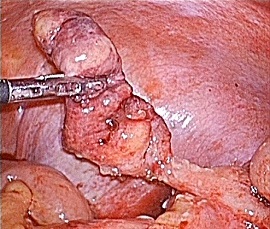

[急性虫垂炎] 手術:腹腔鏡下虫垂切除術(虫垂周囲膿瘍を伴う)

急性腹症のため救急受診。精査の結果、急性虫垂炎と診断。緊急手術(虫垂周囲膿瘍を伴う腹腔鏡下虫垂切除術)を施行した。病理診断結果は急性化膿性虫垂炎であった。

手術画像